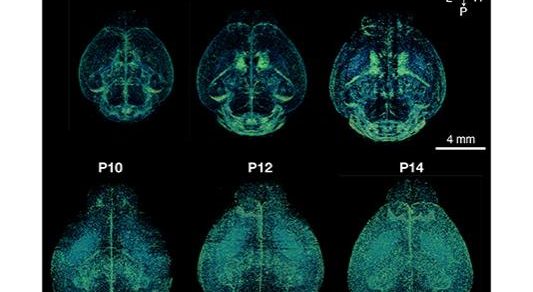

College of Medicine researchers are unlocking the mysteries of the brain in neurodevelopmental disorders like autism and ADHD.